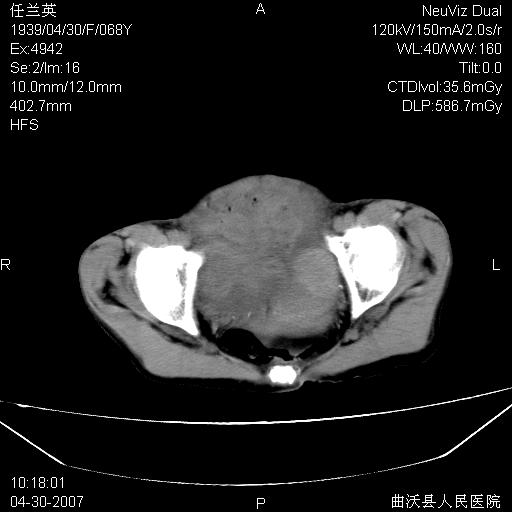

患者,女,68岁,感觉腹部憋涨发硬数天,查b超发现左盆腔有囊性肿物和少量腹水,行ct检查

1.考虑卵巢肿瘤并腹腔广泛性转移可能性大;

2.腹盆腔少量积液。

支持左侧卵巢恶性肿瘤伴网膜、腹膜广泛转移。

支持:左侧卵巢恶性肿瘤伴网膜、腹膜 腹膜后(淋巴结)广泛转移。

难的一见 典型 - 网膜饼  冰冻骨盆 可以当教学片了